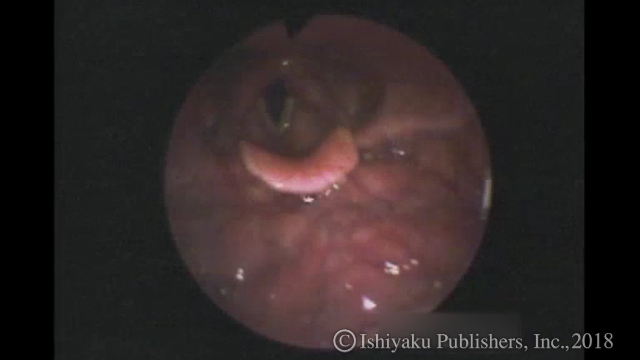

動画1 VE:脳卒中症例